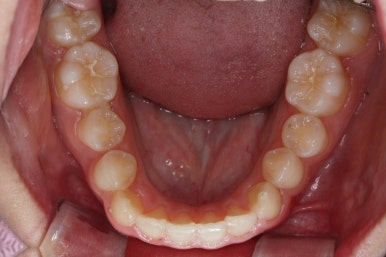

처음 내원 때의 입안 모습입니다.

영구치는 모두 맹출이 되어있었고 아랫니는 윗니에 비해 매우 가지런한 편이였습니다.